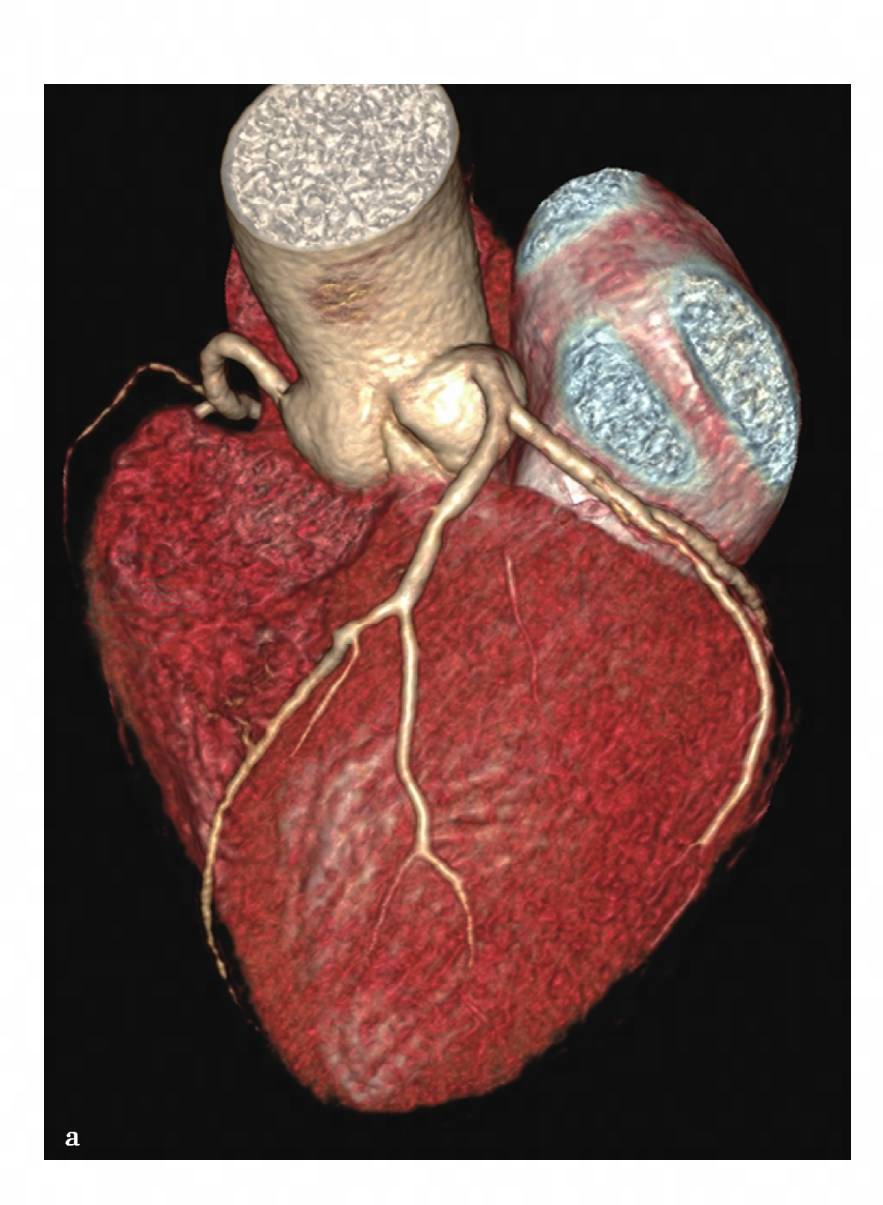

图5 a,VR重组图像,可见前降支近段近段管腔局限性变窄